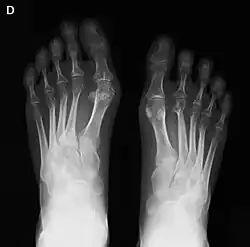

La artritis o inflamación de las articulaciones es la manifestación fundamental de la artritis reumatoide. Las articulaciones afectadas están hinchadas, calientes, dolorosas y rígidas, en especial al levantarse por la mañana o tras el reposo prolongado. Al principio pueden estar afectadas solo una o varias articulaciones, pero progresivamente se van sumando más articulaciones inflamadas —poliartritis—, siendo las que con más frecuencia se afectan las pequeñas articulaciones de las manos y los pies, aunque también es frecuente la afectación de otras articulaciones más grandes como los codos, los hombros, las rodillas o los tobillos.[49] La rigidez matinal es, con frecuencia, un dato destacado de la enfermedad y suele durar más de una hora. Estos datos ayudan a distinguir a la artritis reumatoide de otros problemas no inflamatorios de las articulaciones, como la artrosis u otros tipos de artritis. Las articulaciones se afectan habitualmente de un modo simétrico —afectando articulaciones semejantes en ambos lados del cuerpo—.[50] A medida que la enfermedad progresa, la inflamación articular causa erosiones y destrucción de las superficies articulares y daños tendinosos. Los dedos de las manos pueden sufrir diversas deformidades dependiendo de qué articulaciones y estructuras son las más lesionadas. Son deformidades típicas de la artritis reumatoide evolucionada los dedos en cuello de cisne, la deformidad en ráfaga cubital, la deformidad en boutonniere y el pulgar en Z.[49] La inflamación articular mantenida puede originar daños estructurales en las articulaciones, causando deformidad y pérdida funcional de la articulación afectada.[51][52]

La radiografía convencional es la técnica de imagen estándar de la artritis reumatoide. Los primeros signos radiológicos son la osteoporosis yuxtaarticular y el aumento de partes blandas. Estos cambios se siguen de la disminución del espacio articular, que corresponde a la pérdida de cartílago articular, y la aparición de erosiones óseas en las zonas adyacentes al cartílago articular. El tiempo mínimo para la detección de cambios estructurales en las radiografías está entre 6 y 12 meses, detectándose erosiones radiológicamente en el 50% de los pacientes en el primer año de la enfermedad.[50] En la práctica clínica se utilizan las radiografías para el diagnóstico de la enfermedad, para valorar la gravedad del daño articular y para evaluar su progresión. El ultrasonido y la resonancia magnética son técnicas más sensibles que la radiología convencional.